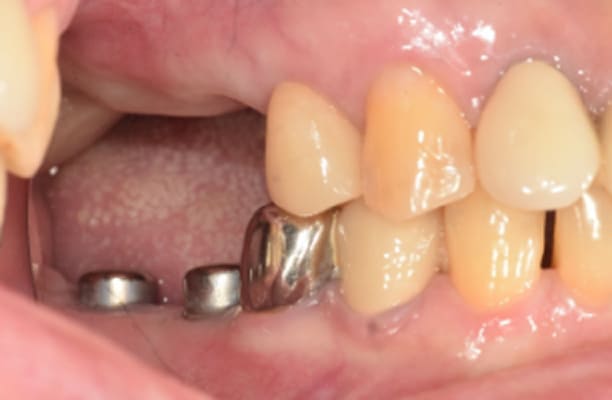

临床案例

-

术前 -

术后